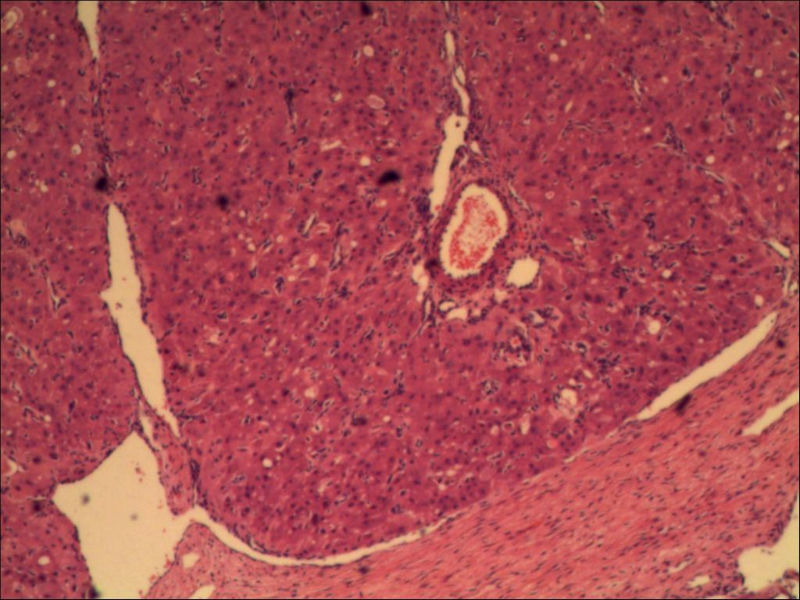

女,27岁,送检右侧卵巢肿物(另外还送检左侧卵巢肿物,大体及镜下显示为畸胎瘤),卵圆形,大小2×1×1cm,似有包膜。卵巢肿物图1

黄体

卵巢黄体

卵巢畸胎瘤中正常卵巢的黄体组织,铺砖样排列,胞浆宽大,较典型。

可能为黄体结节

考虑黄体结节

谢谢大家的回答和解疑,忘记一个重要的病史,就是该女性为产妇。但是妊娠黄体瘤与类固醇细胞瘤怎么鉴别呢

那应该是妊娠黄体/黄体瘤,类固醇细胞瘤有嗜酸细胞和组织细胞样细胞两种,此例显然不是。